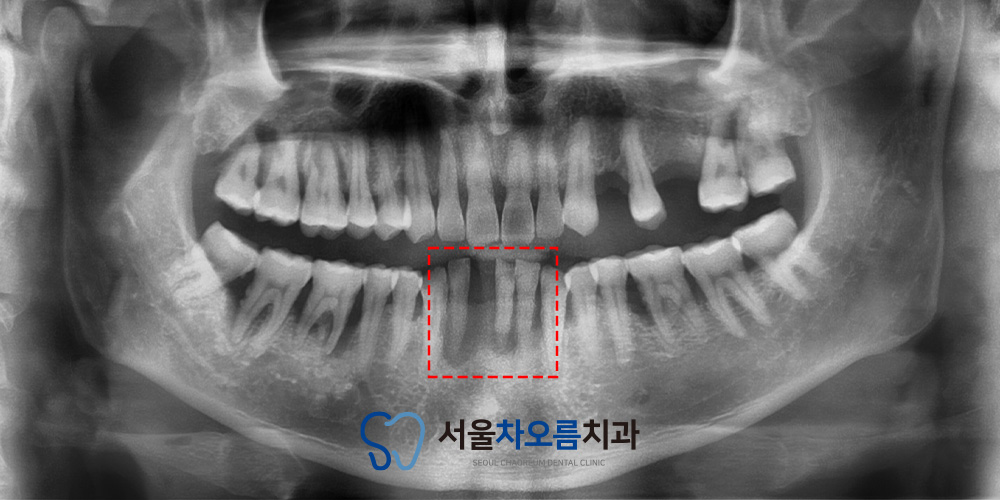

25.11.29 / 26.02.01

치료 전후 사진입니다.

환자분께서는 치아가 하나 없고

주변 치아도 흔들려서

치료를 어떻게 해야하나 막막하셨다고 했지만,

병점치과 365서울차오름의 치료를 통해

심미적이고 기능적인 부분을 전부 개선할 수 있어

다행이라며 만족해 주셨습니다.